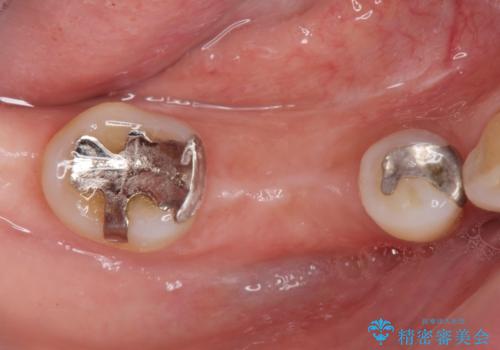

保存できない状態でしたので抜歯をして歯槽堤保存術を行いました。その後大臼歯部にインプラント治療を行いました。

欠損部に1本だけインプラントを埋入しても大きな被せ物になってしまい清掃性が悪くなるので清掃性が良くなるように2本小臼歯用のインプラントを埋入しました。

また1番奥の歯はセラミックインレーで治療を行いました。